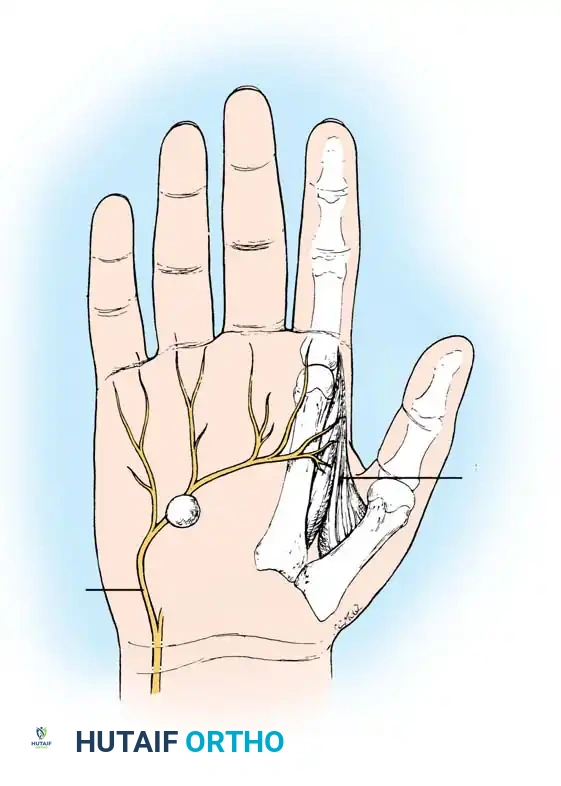

Ganglions seldom occur deep in the palm. When they do, their presence is often heralded not by an external mass, but by secondary neurological changes caused by mass effect. For instance, cysts arising in or distal to Guyon's canal can cause profound motor neuropathy.

Ganglion in the palm producing pressure on the deep branch of the ulnar nerve, causing severe atrophy of the first dorsal interosseous muscle.